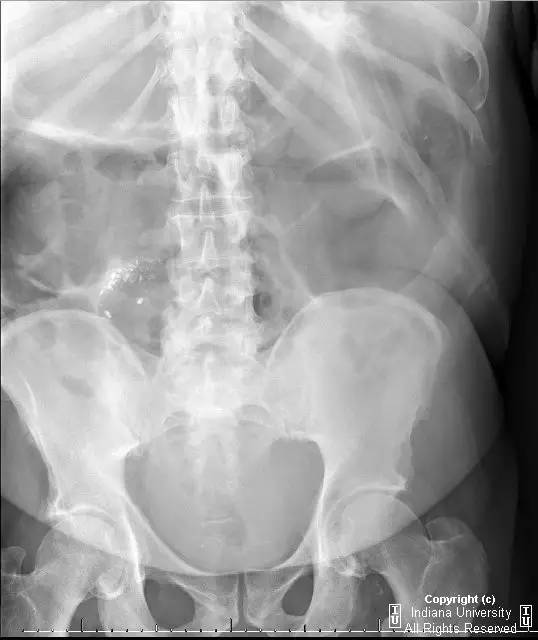

【病史】男性,腹胀。

注意右下腹弯曲串珠样密度影,你的考虑可能为?

【答案】1.A 2.E 3.C

【影像学表现】右侧腹部可见曲线样不透亮区,1周后位置有变化(似进入盲肠)。横结肠显著扩张、充气。CT上扩张原因不明,无明确的梗阻证据。

【诊断】阑尾内对比剂充填